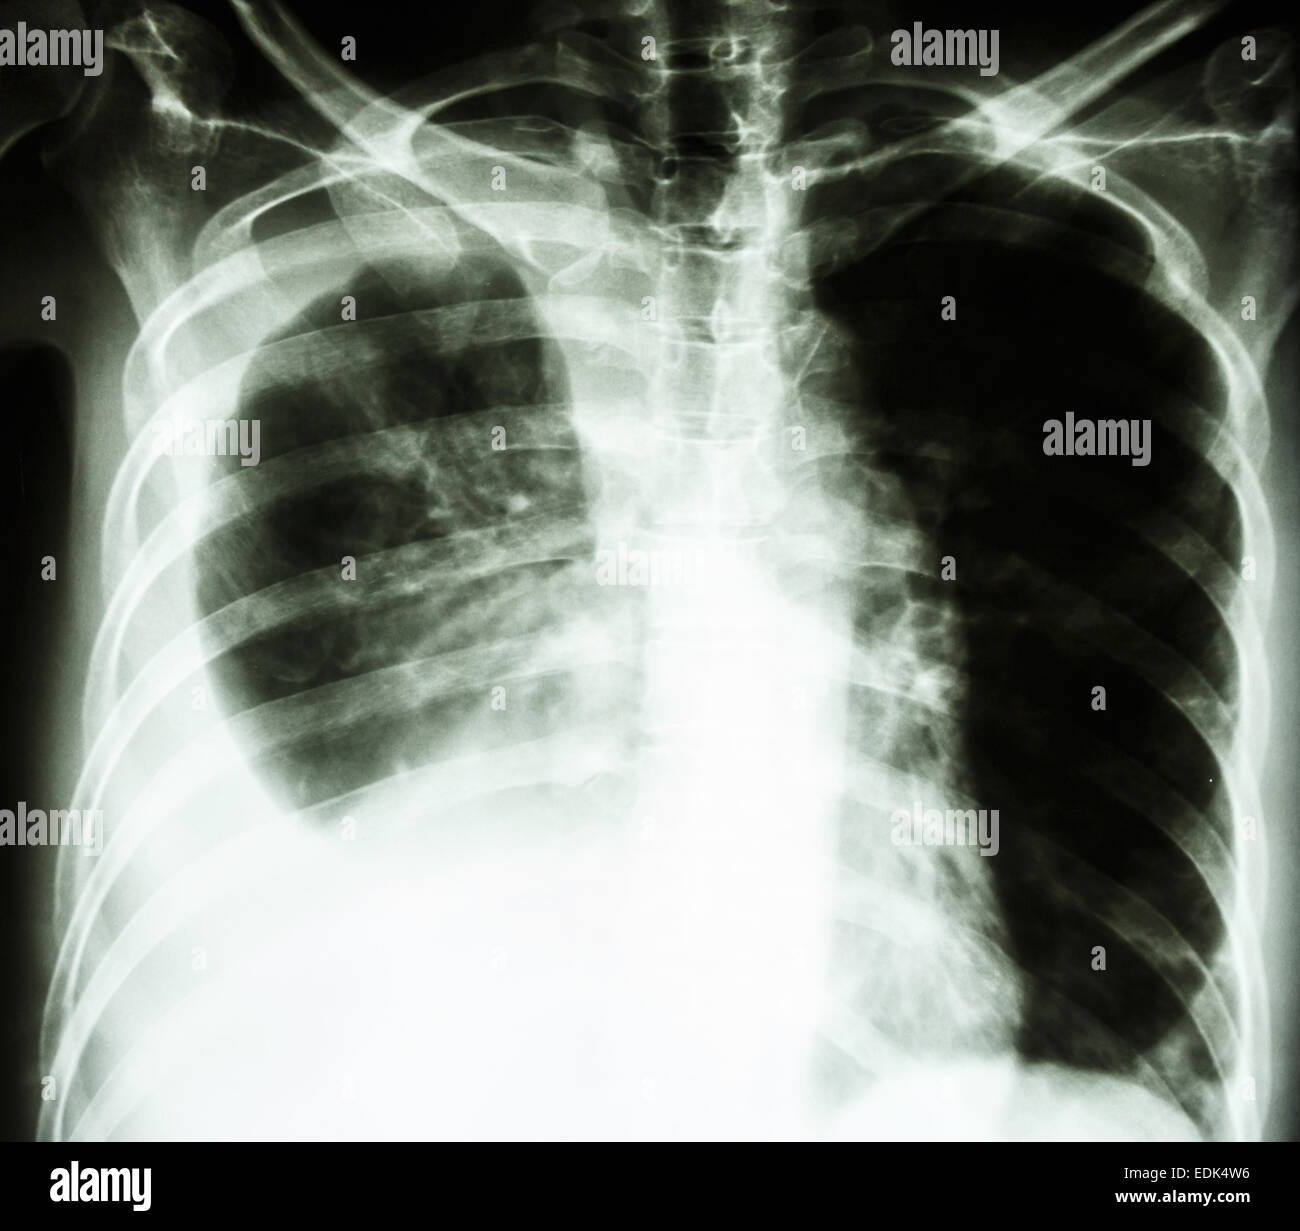

film chest Xray PA upright show pleural effusion at right lung due Fluid In Lungs Chest X Ray Tests that can help diagnose pulmonary edema or determine the reason for fluid in the lungs include: There are many causes of pleural effusion that are broadly split into transudates and exudates. You may have symptoms, such as chest pain,. Pleural effusion, also called water on the lung, happens when fluid builds up in the space between your lungs and. Fluid In Lungs Chest X Ray.

A chest xray film of a patient with massive pleural effusion. Fluid in Fluid In Lungs Chest X Ray There can also be fluid in other parts of the chest like in the mediastinum, along the. Some people may also have a. Pleural effusion, also called water on the lung, happens when fluid builds up in the space between your lungs and chest cavity. Tests that can help diagnose pulmonary edema or determine the reason for fluid in the. Fluid In Lungs Chest X Ray.